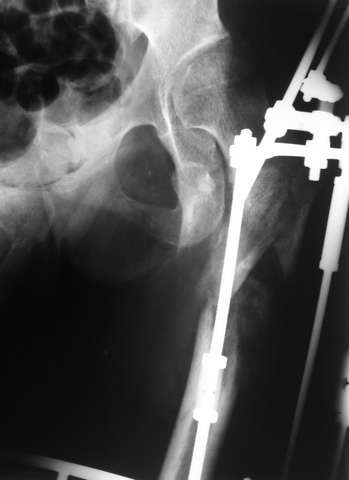

Девушка 21 года 02.10.07 г. пострадала в результате падения с высоты 4-го этажа при пожаре в одном из студенческих общежитий г. Москвы. Получила тяжелую сочетанную травму, в том числе закрытый оскольчатый чрез- и подвертельный перелом левой бедренной кости. Лечилась в одной из больниц столицы. Бедро было фиксировано при помощи скелетного вытяжения. Через полтора месяца после травмы переведена в институт им. Склифосовского. У больной имелись: поддиафрагмальный абсцесс, трахеопищеводный свищ, трахеостома, гастростома, несостоятельность швов раны передней брюшной стенки, укорочение левого бедра на 10 см (рентгенограммы при поступлении - рис 1.). В середине декабря был наложен спицестержневой аппарат, с помощью которого к сегодняшнему удалось устранить укорочение бедра (рис. 2). В течение последних 4-х дней устраняем смещение дистального отломка бедренной кости по ширине. Раны на передней брюшной стенке почти зажили. Температура тела и лабораторные показатели нормальные. Планируем выполнить закрытый остеосинтез левой бедренной кости удлиненным проксимальным бедренным штифтом производства фирмы "Остеомед". Нас смущает, что малый вертел бедренной кости остается значительно смещенным проксимально и кнутри.

Мы закончили репозицию отломков бедренной кости в аппарате (рис. 1, 2) у нашей пациентки и на прошлой неделе сделали ей вторую операцию. Штифт удалось ввести закрыто. Верхний шеечный винт держался очень плохо, поэтому мы его убрали и решили не ставить. Нижний держал очень плотно. Рентгенограммы после операции прилагаю (рис. 3,4). Пока не получилось сделать нормальный аксиальный снимок (больная с трудом сгибает и отводит ногу в тазобедренном суставе). Пока сделали боковую проекцию в положении на здоровом боку со сгибанием здоровой ноги.